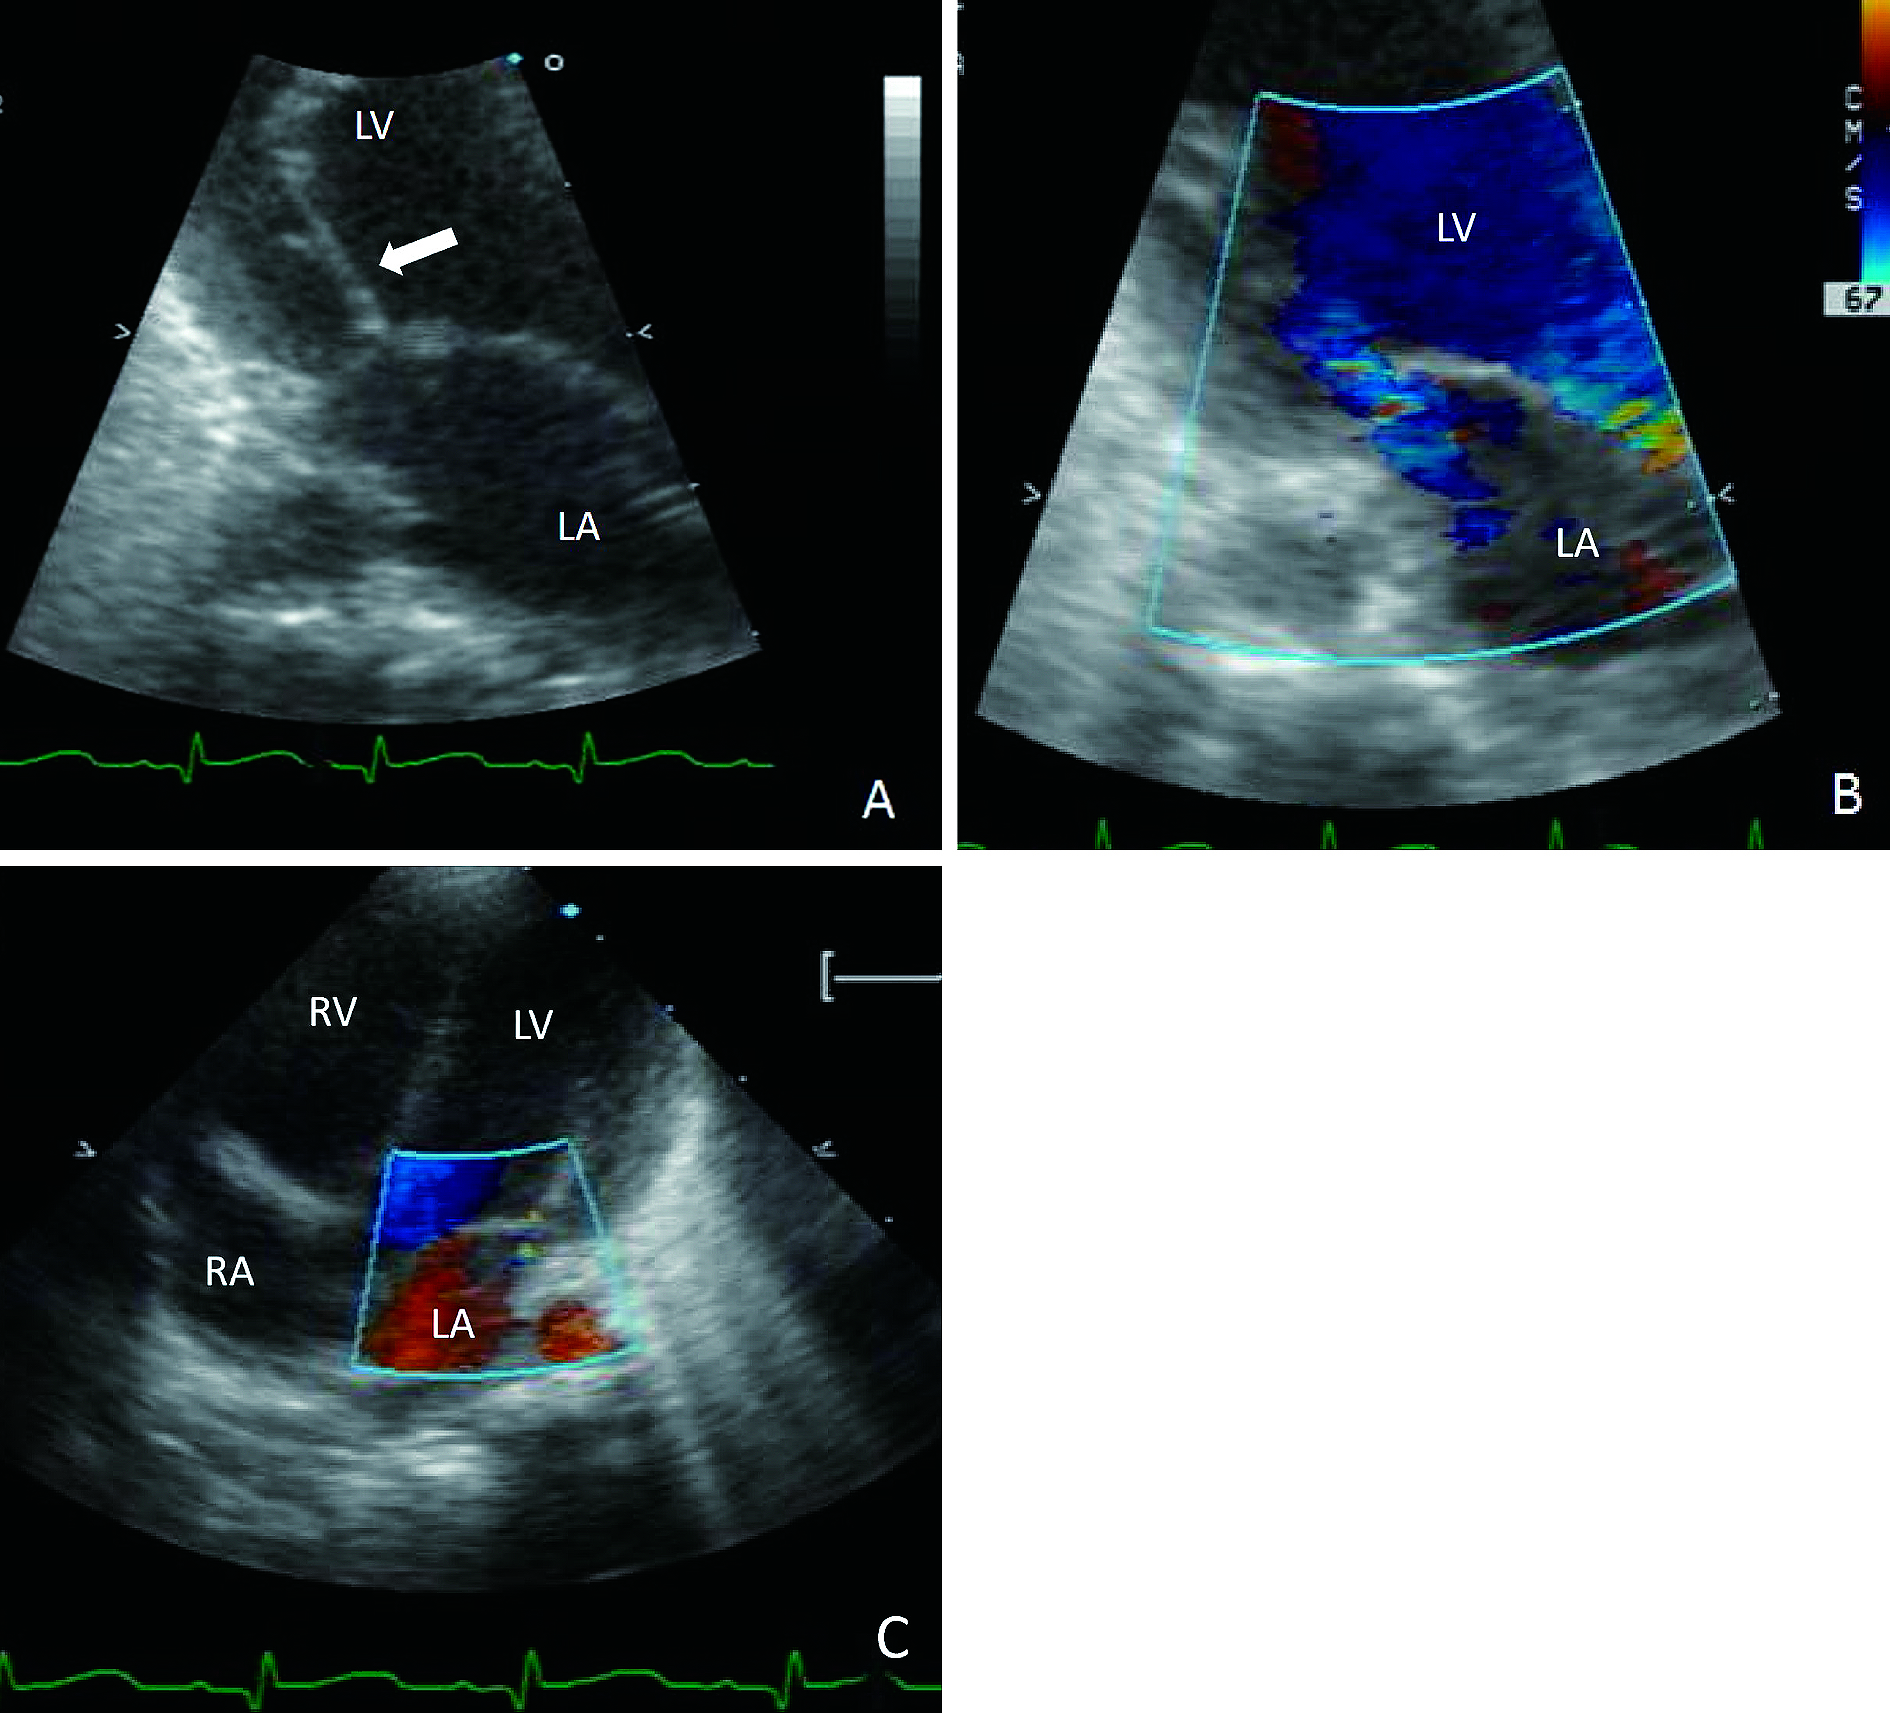

「緊急修復術により救命した乳児突発性憎帽弁腱索断裂例」 - ・第116巻8号 P1223 越智 史博,他